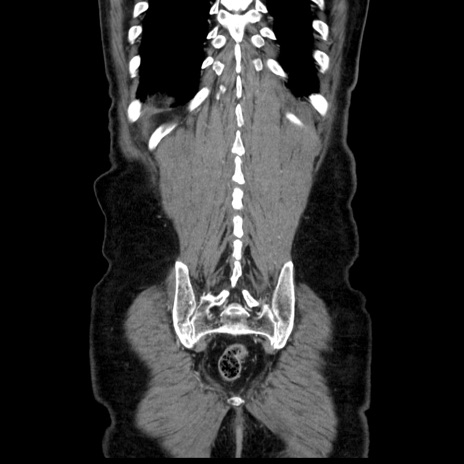

症例30(冠状断像)

【症例】80歳代男性

【主訴】臍周囲痛

【現病歴】約6時間前から臍下部痛が出現。次第に腹部膨隆・背部痛も生じてきたため来院。背部痛の場所は変化しない。

【身体所見】意識清明、BT 36.3℃、BP  131/87mmHg、P 87bpm、SpO2 100%(RA)、臍周囲自発痛・圧痛あり、反跳痛なし、自発痛部位に一致して板状硬あり、腹部膨隆、腸雑音減弱、CVA tenderness両側陰性。

【データ】WBC 19600、CRP 0.33